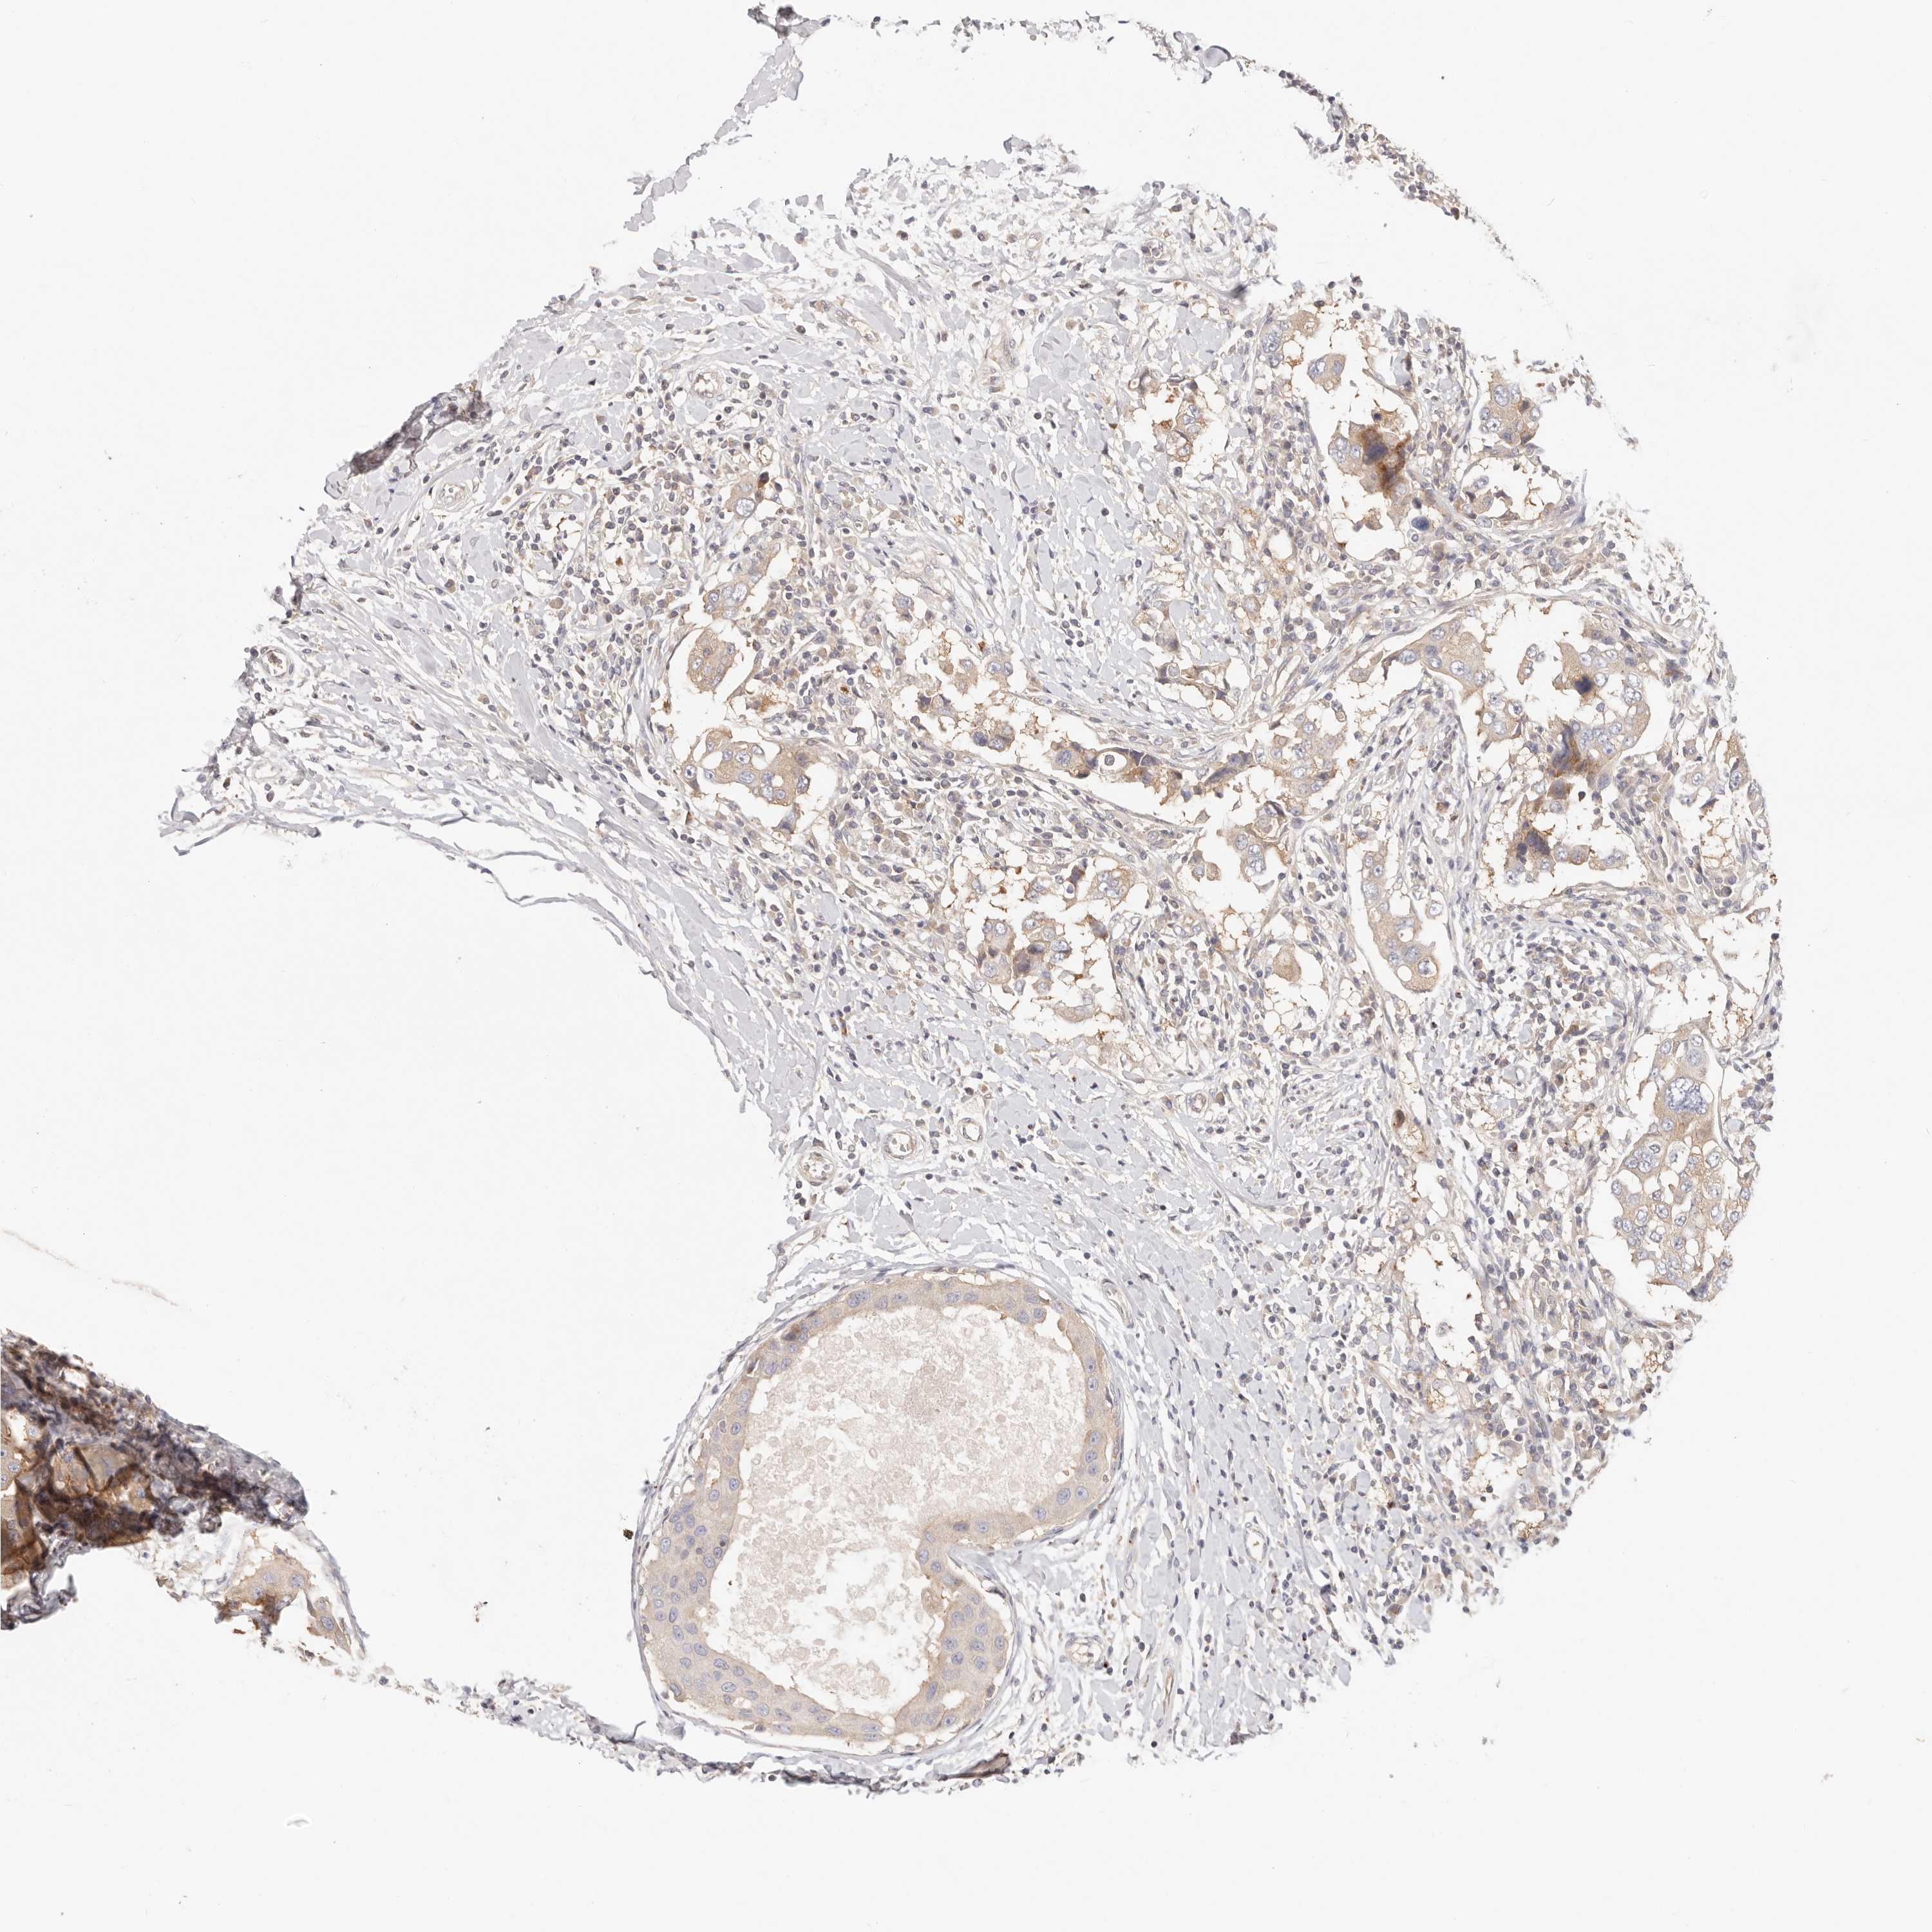

CANCER BREAST CANCER Show tissue menu

BRCA TCGA BRCA VALIDATION PROTEIN EXPRESSION